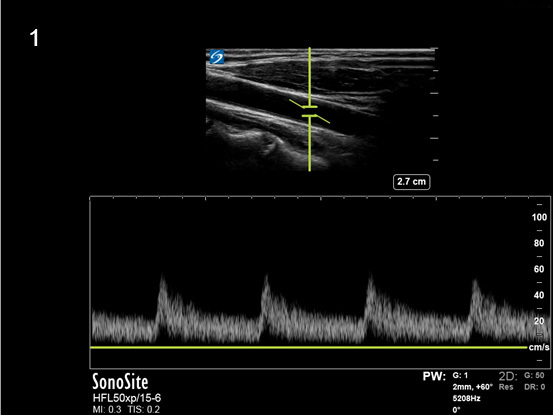

Instrumentation Pulse Wave Doppler Low Gain Image